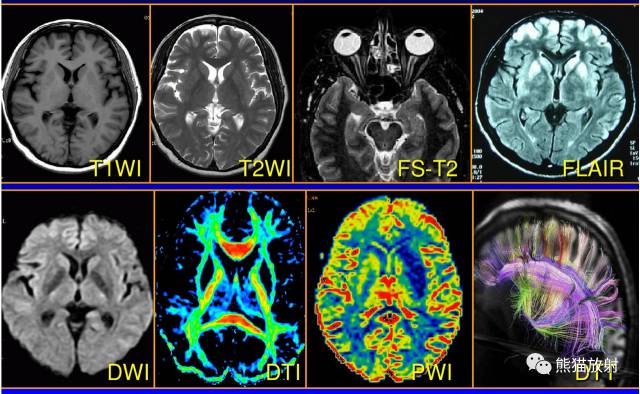

液体衰减反转恢复(FLAIR)序列图像有何特点

液体衰减反转恢复的英文简称是FLAIR(fluid-attenuated inversion recovery),是反转恢复序列的一种变型。

FLAIR序列是一种反转恢复脉冲序列,它利用各种组织的T1值不同,在产生信号的90°激励脉冲前施加一个180°的反转脉冲,经过适当的时间(反转时间),脑脊液在90°脉冲作用时纵向磁化矢量为零,使脑脊液的T1值为零,从而不产生MR信号;而颅内其他组织的T1值明显短于脑脊液,在90°脉冲时纵向磁化矢量已几乎完全恢复,仍可以产生MR信号。这样FLAIR序列使用长反转时间 (inversion time,TI)抑制脑脊液的信号,使用长重复时间(repetitiontime,TR)和长回波时间(echo time,TE)产生重T2加权像。

T2 FLAIR序列的TI 较长,通常为1700~2500ms(与场强有关),能够有效抑制游离水或正常脑脊液的MR信号,形成水抑制图像(抑水像),多用于脑部和脊髓成像,如显示多发性硬化斑块、颅内胆脂瘤、蛛网膜下腔出血和脑膜炎等病变。

T2 FLAIR能更清楚显示在常规T2WI被脑脊液高信号掩盖的病变,尤其在脑室周围、脑表面、蛛网膜下腔区域,提高诊断的敏感性。

在一些超高场强MRI系统,为提高组织对比度,在脑部成像时常以T1 FLAIR序列取代SE或FSE T1WI。相对于T2 FLAIR中扫描参数,T1 FLAIR序列中的TI和TE均较短。